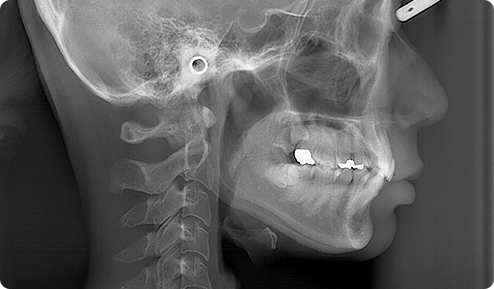

頭部X線規格写真ともいわれるセファログラムは、顎の骨の形や角度、歯の生えている方向などを一定の基準に従って分析するためのレントゲン撮影技法です。特殊なレントゲン撮影であるため、一般の歯科医院にはあまり置かれていませんが、しっかりとした矯正治療を行う上で欠かせないものです。

CT撮影では三次元の画像を得ることが出来るので、従来の平面レントゲン画像に比べはるかに豊富な情報を得ることが出来ます。矯正治療では歯を顎骨内で三次元的に動かしていくので、従来のレントゲン画像だけでは顎骨や歯の十分な判断が難しいケースがあり、より正確な診断のためにCTが有効です。また顎骨内に歯が埋まっている場合、歯の正確な位置を把握することが出来ます。